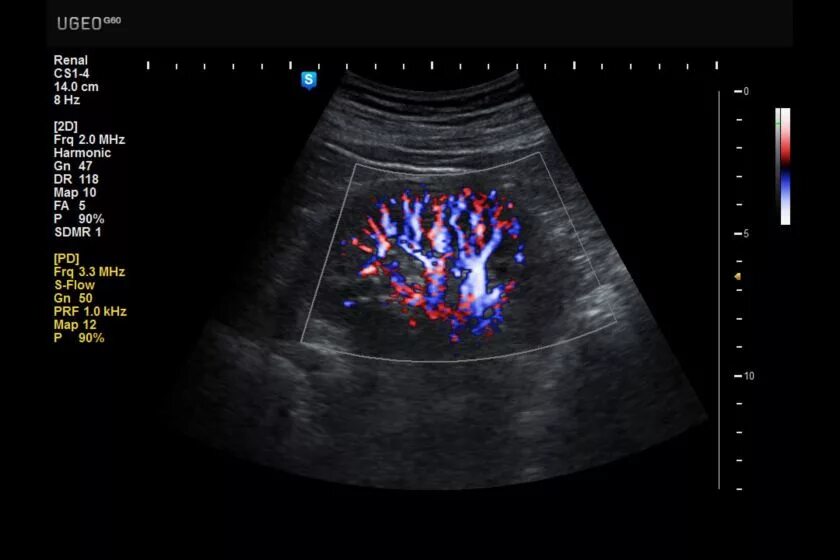

Узи сердца узи почек